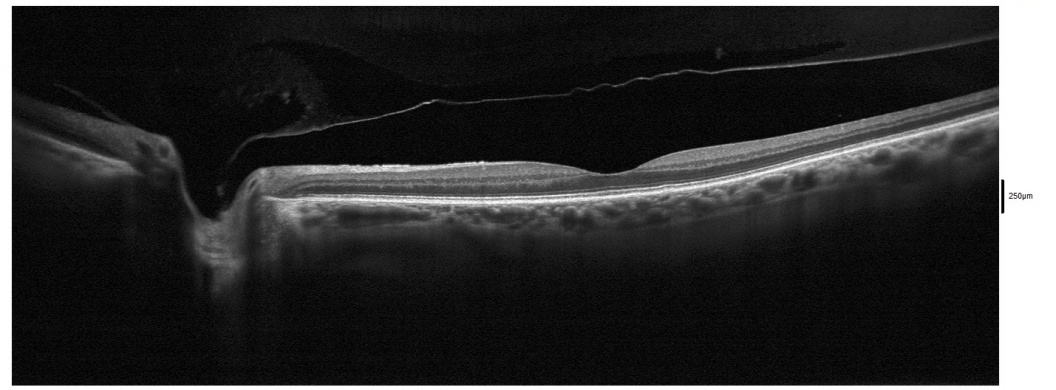

Posterior Vitreous Detachment (PVD) is a separation between the posterior vitreous cortex and the neurosensory retina, with the vitreous collapsing anteriorly towards the vitreous base. Changes occur with advancing age in the enzymatic activities in the vitreous and vitreoretinal interface that promote vitreous separation from the inner retinal surface. [1]

The initial event is liquefaction and syneresis of the central vitreous. A rupture develops in the posterior hyaloid (or vitreous cortex) through which liquefied vitreous flows into the retrovitreous space, separating the posterior hyaloid from the retina. It typically starts as a partial PVD in the perifoveal region and is usually asymptomatic until it progresses to the optic disc, when separation of the peripapillary glial tissue from the optic nerve head occurs, usually with formation of a Weiss ring and accompanying symptoms.

There are no surgical indications for routine PVDs. If a partial PVD is present that is causing vision threatening vitreomacular traction syndrome, pars plana vitrectomy with membrane peeling may be indicated. Resolution occurs in half of patients with VMT; others may progress to a lamellar hole or a macular hole. Serial OCT scans can be used to assess for progression every 1-3 months.